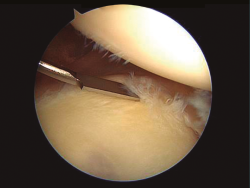

En la imagen pueden apreciarse pequeñas lesiones capsuloligamentosas y del labrum, características de los cuadros de inestabilidad, en un paciente que presentaba sintomatología de dolor sin episodios de luxación y un signo clínico común con otras formas de inestabilidad: la aprensión.